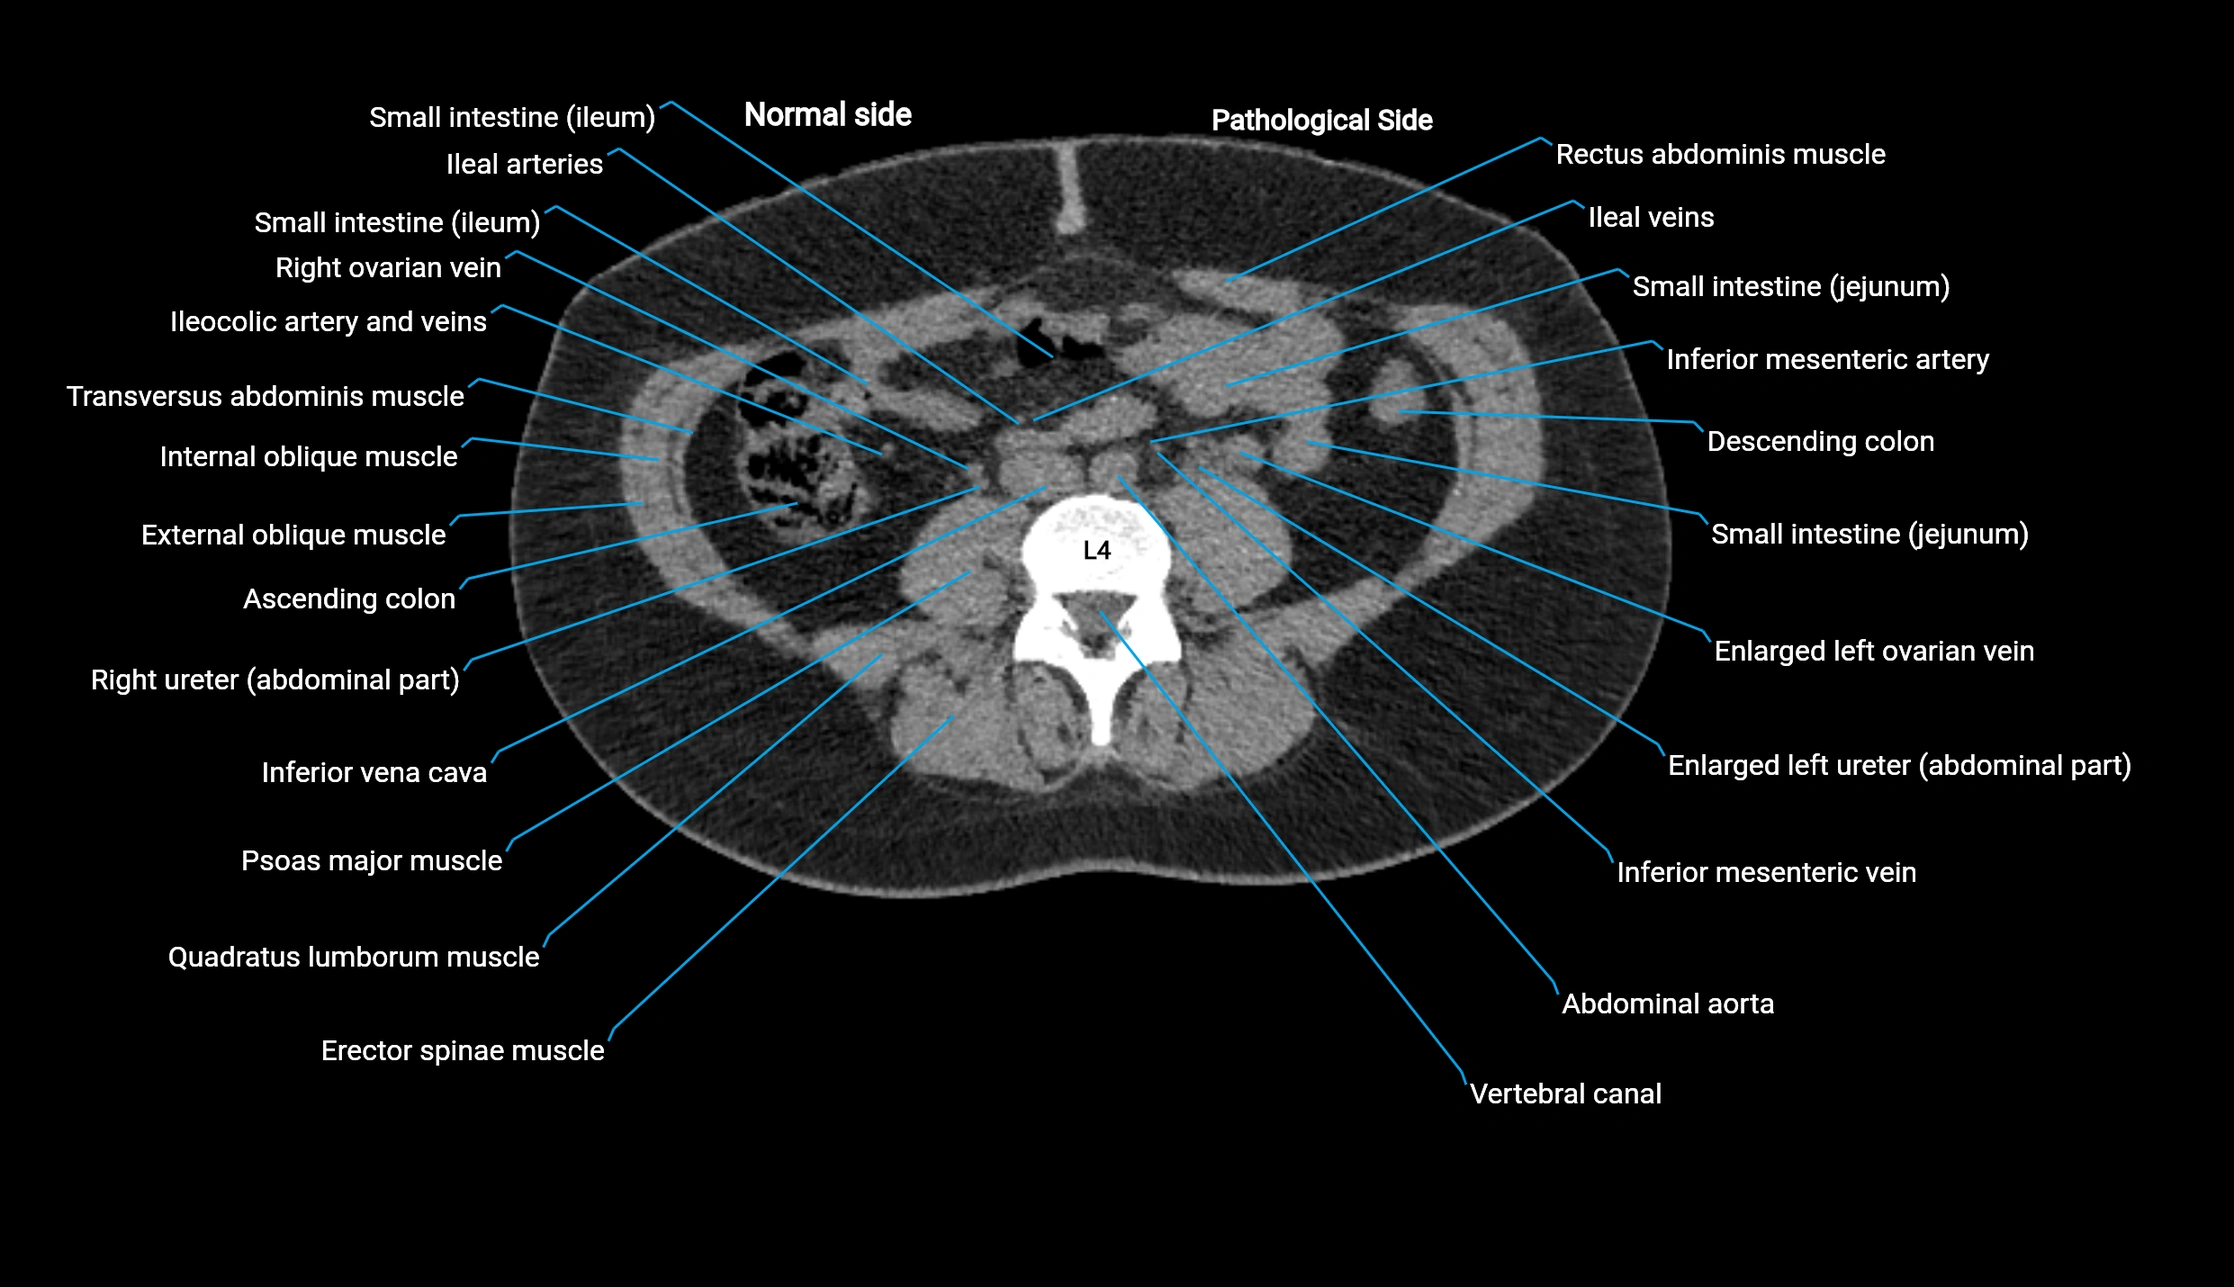

CT image

image